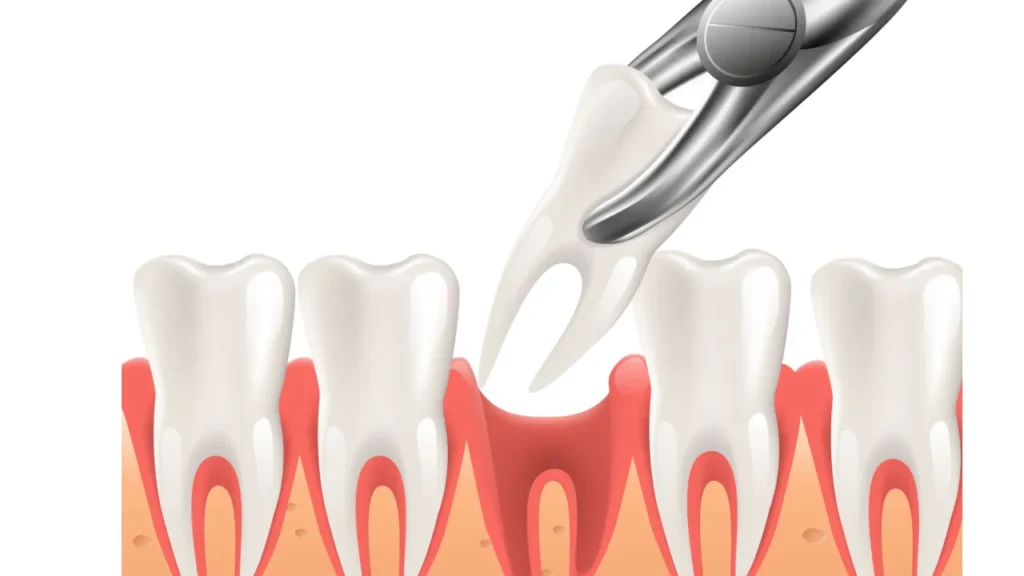

Severe decay:

When a tooth is extensively decayed and cannot be restored through a filling or root canal treatment, extraction may be necessary.